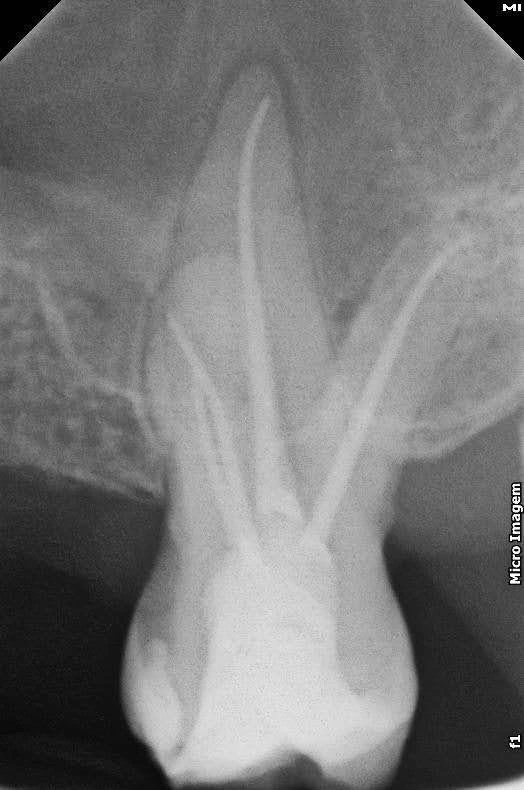

Endodontia (antes)

Endodontia

O que é?

O tratamento endodôntico ocorre geralmente por cárie profunda, infiltrações ou fratura dental que compromete o nervo (a polpa) dos dentes. Quando isso acontece a pessoa sente muita dor. Às vezes a dor é espontânea, pulsátil e intensa. E costuma durar várias horas, sem cessar.

Aqui o tratamento de canal é realizado sem dor e sem trauma. Com técnicas mais modernas de anestesia, instrumentação rotatória, raio-x digital e, quando possível, realizamos os canais em sessão única.

Esse trabalho é realizado pelo especialista em endodontia, Dr. Lucas Ribeiro.